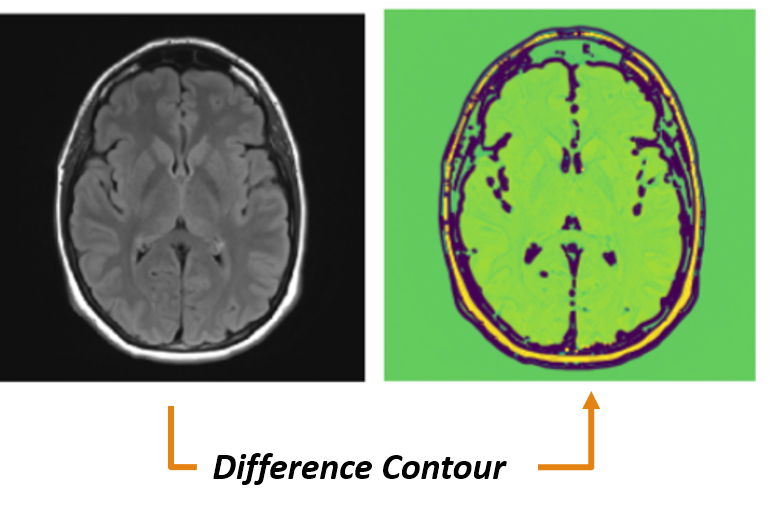

(c) Difference contour for gray scale MRI image

Figure 6: An example of special preprocessing technique.

Differencing: In this phase, the matrices of grayscale MRI image is subtracted from the Sobel edge MRI image are on a pixel by pixel basis. If different contour intensity is present in original contour and Sobel edge contour then take the higher value of intensity. This phase reduced the less oriented regions and gave proper intensity uplifting in the regions of interest. An example showing the contour matching operation over the difference image for an MRI sample is shown in Fig. 6(c).